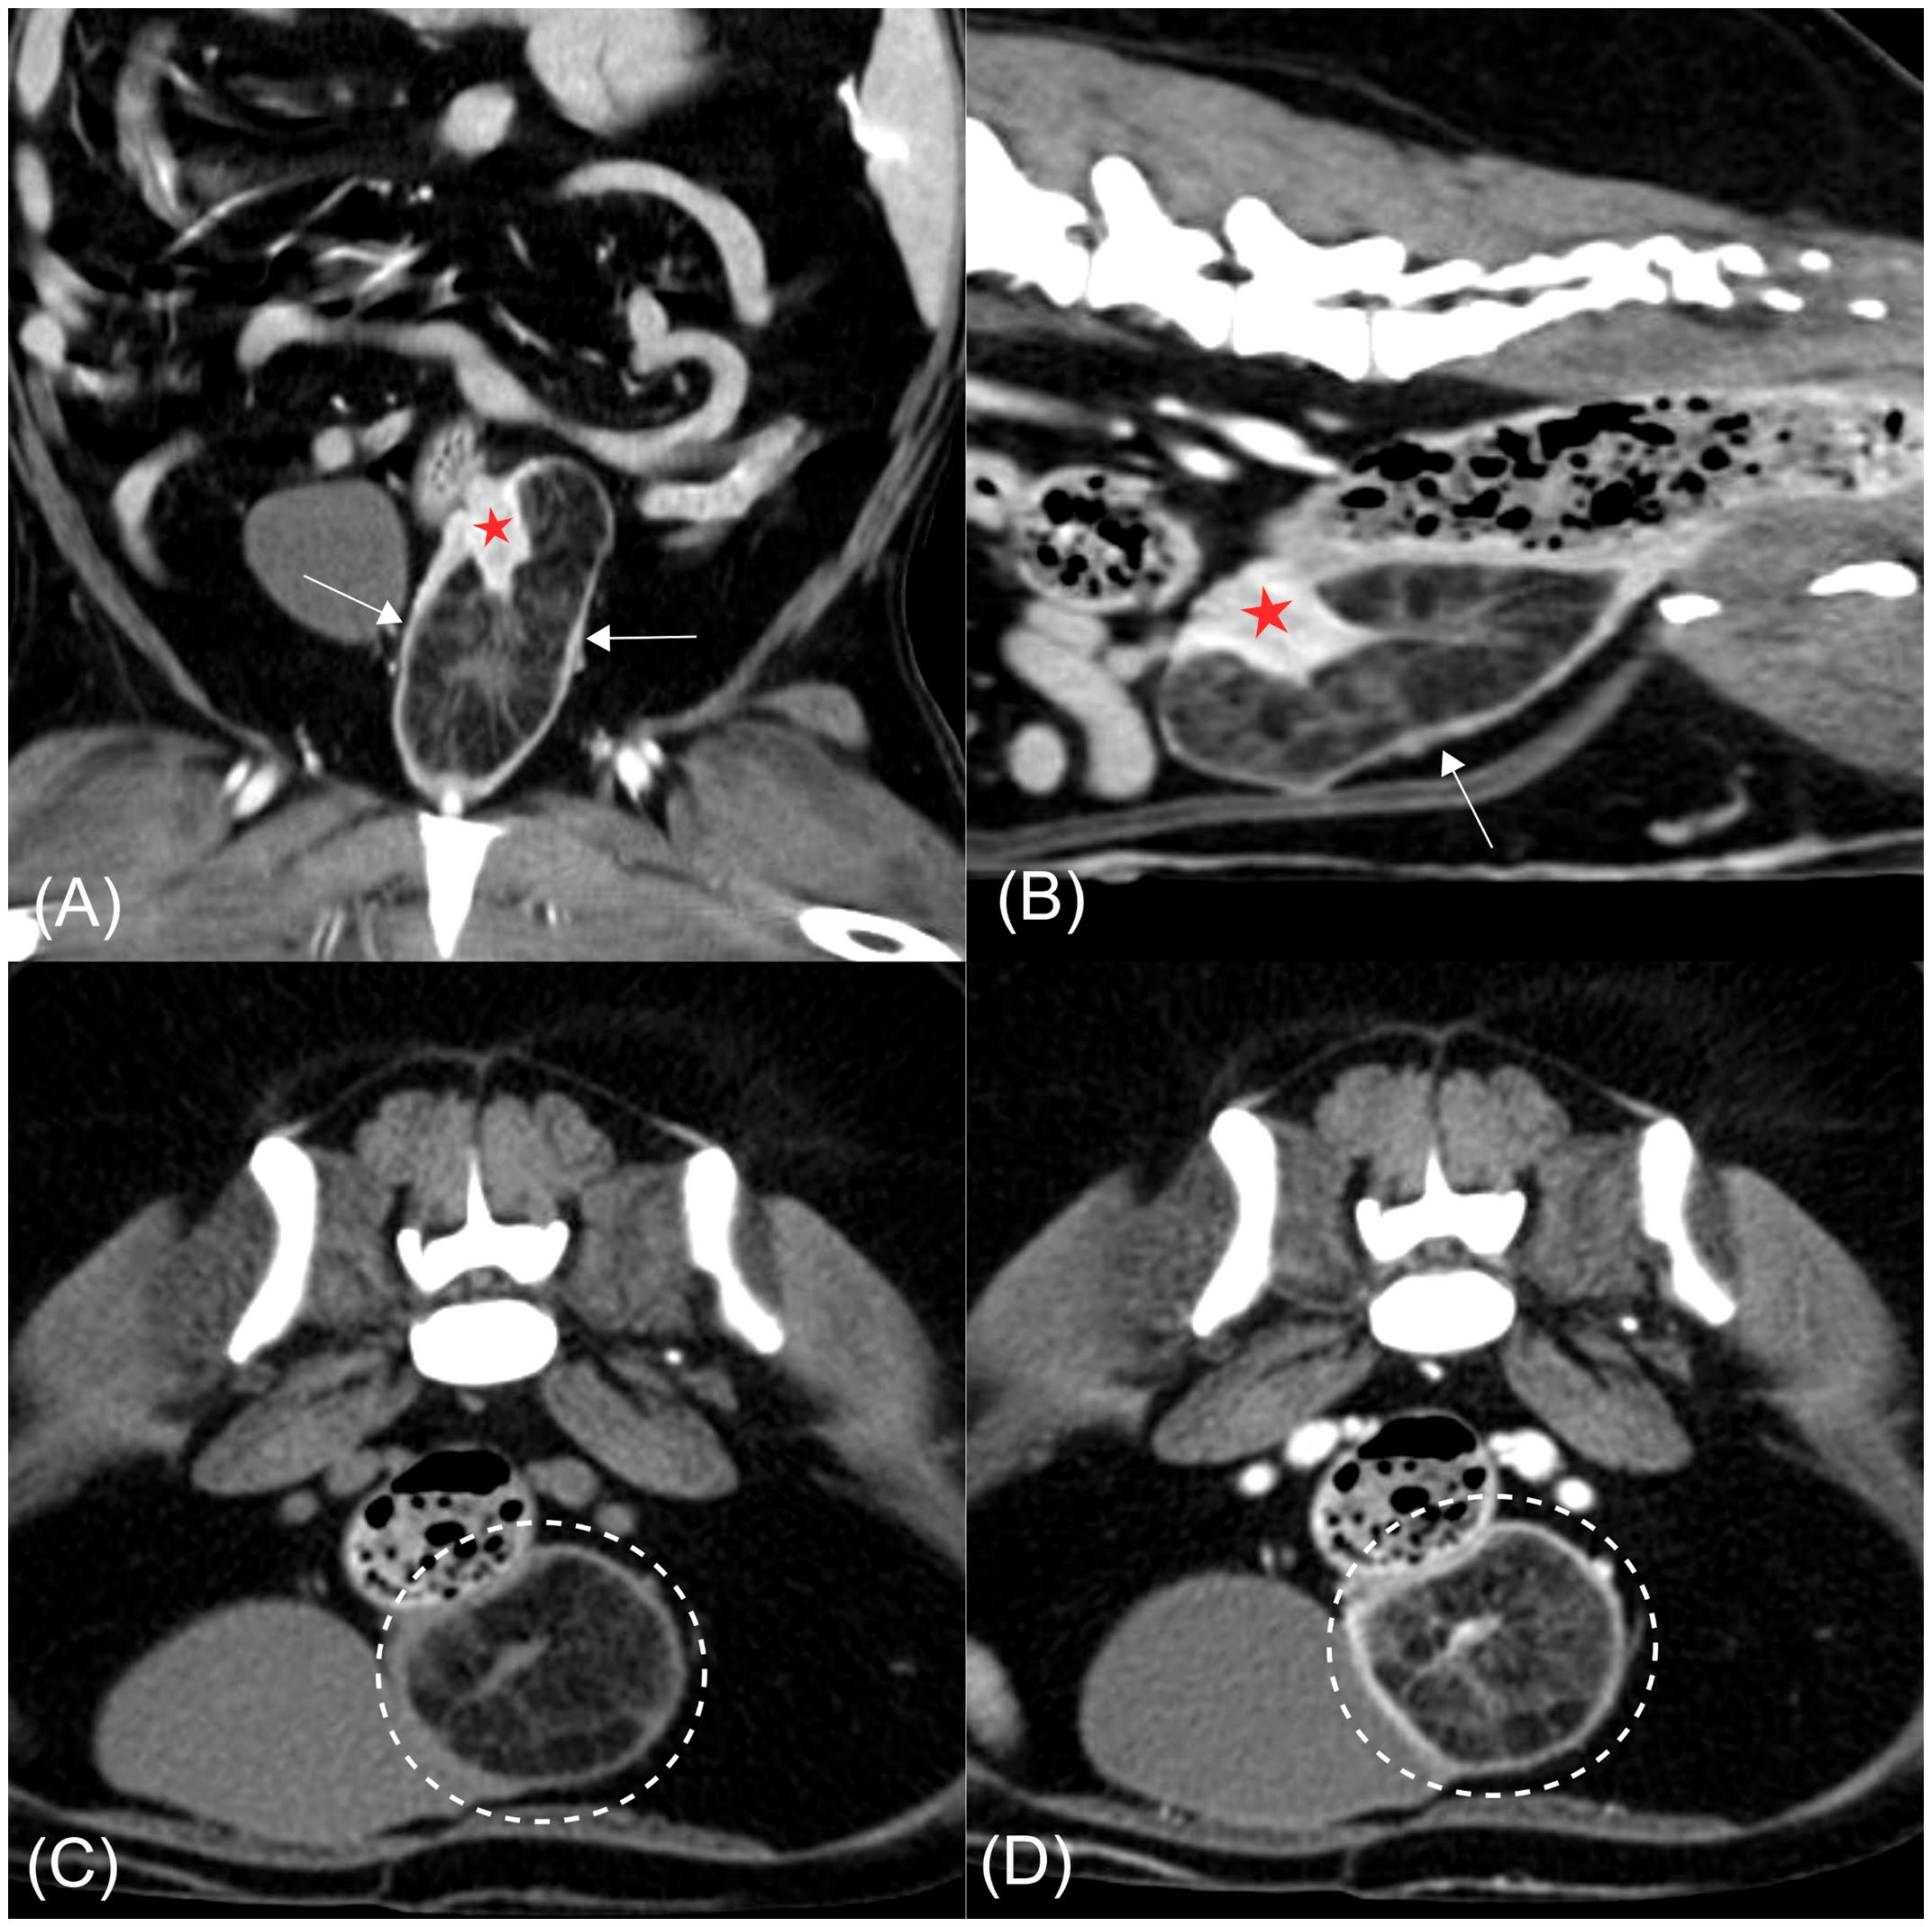

CT显示一界限清晰的低密度肿块,约37×35×73 mm,内含管腔内软组织密度条纹,定位于宫颈水平,并部分突入阴道前段。宫颈似部分内陷进入该低密度肿块,其内部条纹与宫颈组织相延续(图2AB)。内陷的宫颈壁轻度增厚,且相对于阴道明显强化。既往研究报道宫颈增强程度高于阴道,CT值亦更高。本例内陷宫颈壁的显著强化与上述结果一致(宫颈183 HU;阴道160 HU),支持肿块源于宫颈而非阴道。子宫角及宫颈尚见轻度壁增厚及多发小囊性灶,双侧卵巢未见异常。宫颈平扫及增强平均CT值分别为50 HU与184 HU,符合软组织密度;与宫颈相连的条纹组织平扫23 HU、增强63 HU,亦属软组织范围。肿块内的低密度区平扫−113 HU、增强−90 HU,符合脂肪密度(图2CD)。

图2. (A) 增强后冠状面图像。(B) 增强后矢状面图像。(C) 平扫横断面图像。(D) 增强后横断面图像。宫颈水平可见一界限清晰的低密度肿块,部分突入阴道前段(箭头)。肿块内可见与部分内陷且明显强化的宫颈壁相延续的软组织密度条纹(红色星号)。在横断面图像(CD)中,肿块内的低密度区域符合脂肪密度,增强后仍无强化(虚线圆圈)。